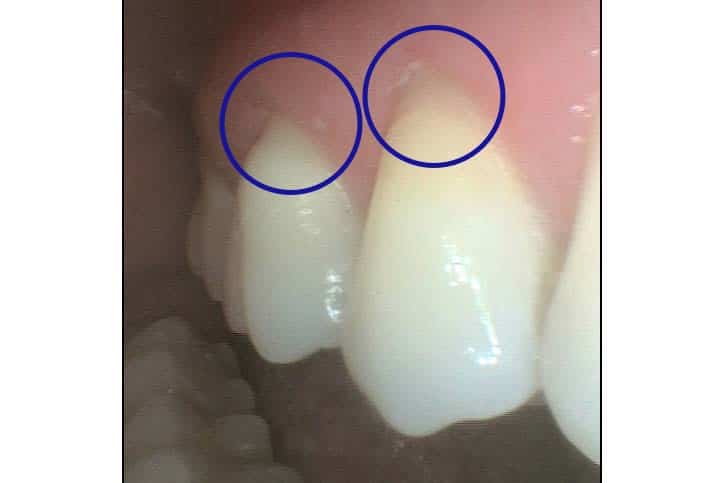

Før- og etterbilder